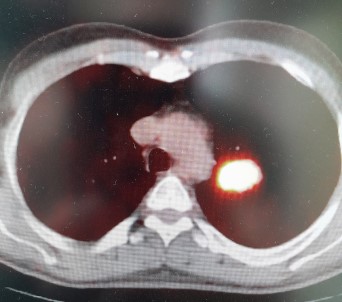

Bu durumda kisiyi kanserden kurtaracak en etkili yöntemin erken tani ve tedavi olanaklari olduguna dikkat çeken Özkaya, pandeminin kanser konusunda topluma önemli bir katkisi oldugunu anlatti. Covid-19 nedeniyle basvuran hasta sayisinda ve radyolojik görüntülemelerde yasanan artisin birçok vakanin erken evrede saptanmasini sagladigini belirtti.